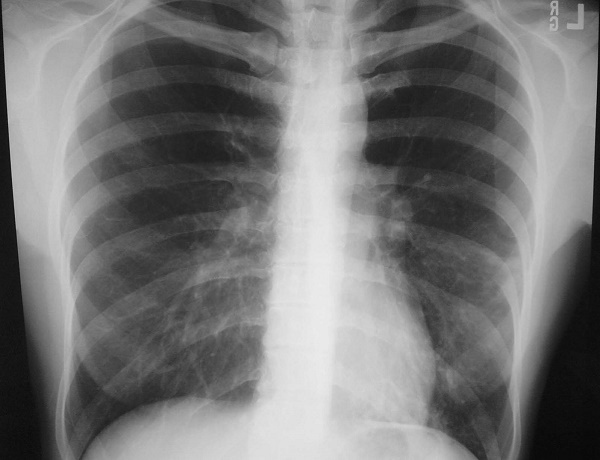

Viêm phổi là nguyên nhân tử vong hàng đầu ở trẻ em trên thế giới. Không những vậy, viêm phổi cũng có thể gặp ở người lớn. Các bác sĩ khuyến cáo người dân không nên chủ quan trước những nguyên nhân gây viêm phổi.

Viêm phổi là nguyên nhân mắc bệnh và tử vong hàng đầu ở trẻ em trên thế giới, nhất là tại các nước đang phát triển như nước ta. Bệnh có thể diễn tiến với 3 mức độ từ nhẹ đến nặng và rất nặng. Nếu không được xử trí đúng và kịp thời có thể dẫn đến suy hô hấp và tử vong.

Viêm phổi là bệnh lý viêm nhiễm của nhu mô phổi thường do virut, vi khuẩn, nấm hay ký sinh trùng gây ra. Viêm phổi có mức độ từ nhẹ đến đe dọa tính mạng. Bệnh có thể lây truyền từ người này sang người khác. Đặc biệt viêm phổi do virut có thể gây thành dịch nguy hiểm và ở trẻ càng nhỏ, diễn biến bệnh càng nhanh và nặng.

Triệu chứng viêm phổi

Trẻ mắc bệnh viêm phổi hay có các triệu chứng như: sốt, nhức đầu, ho khan hoặc ho có đàm, thở nhanh, đau ngực, mệt mỏi, gầy sút, nghe phổi có tiếng ran. Khi trẻ bị khó thở, cha mẹ có thể phát hiện bệnh viêm phổi ở trẻ bằng cách đếm nhịp thở của trẻ trong một phút bằng một đồng hồ có gắn kim giây.

Nếu trẻ có thở nhanh theo lứa tuổi là trẻ bị viêm phổi. Viêm phổi nặng khi cha mẹ quan sát thấy 1/3 ngực dưới của trẻ bị lõm vào khi hít vào (bình thường 1/3 ngực dưới đầy lên khi hít vào). Viêm phổi rất nặng khi trẻ có kèm thêm các dấu hiệu sau: nôn tất cả mọi thứ, không bú được hay bỏ bú, li bì khó đánh thức, co giật, tím tái.